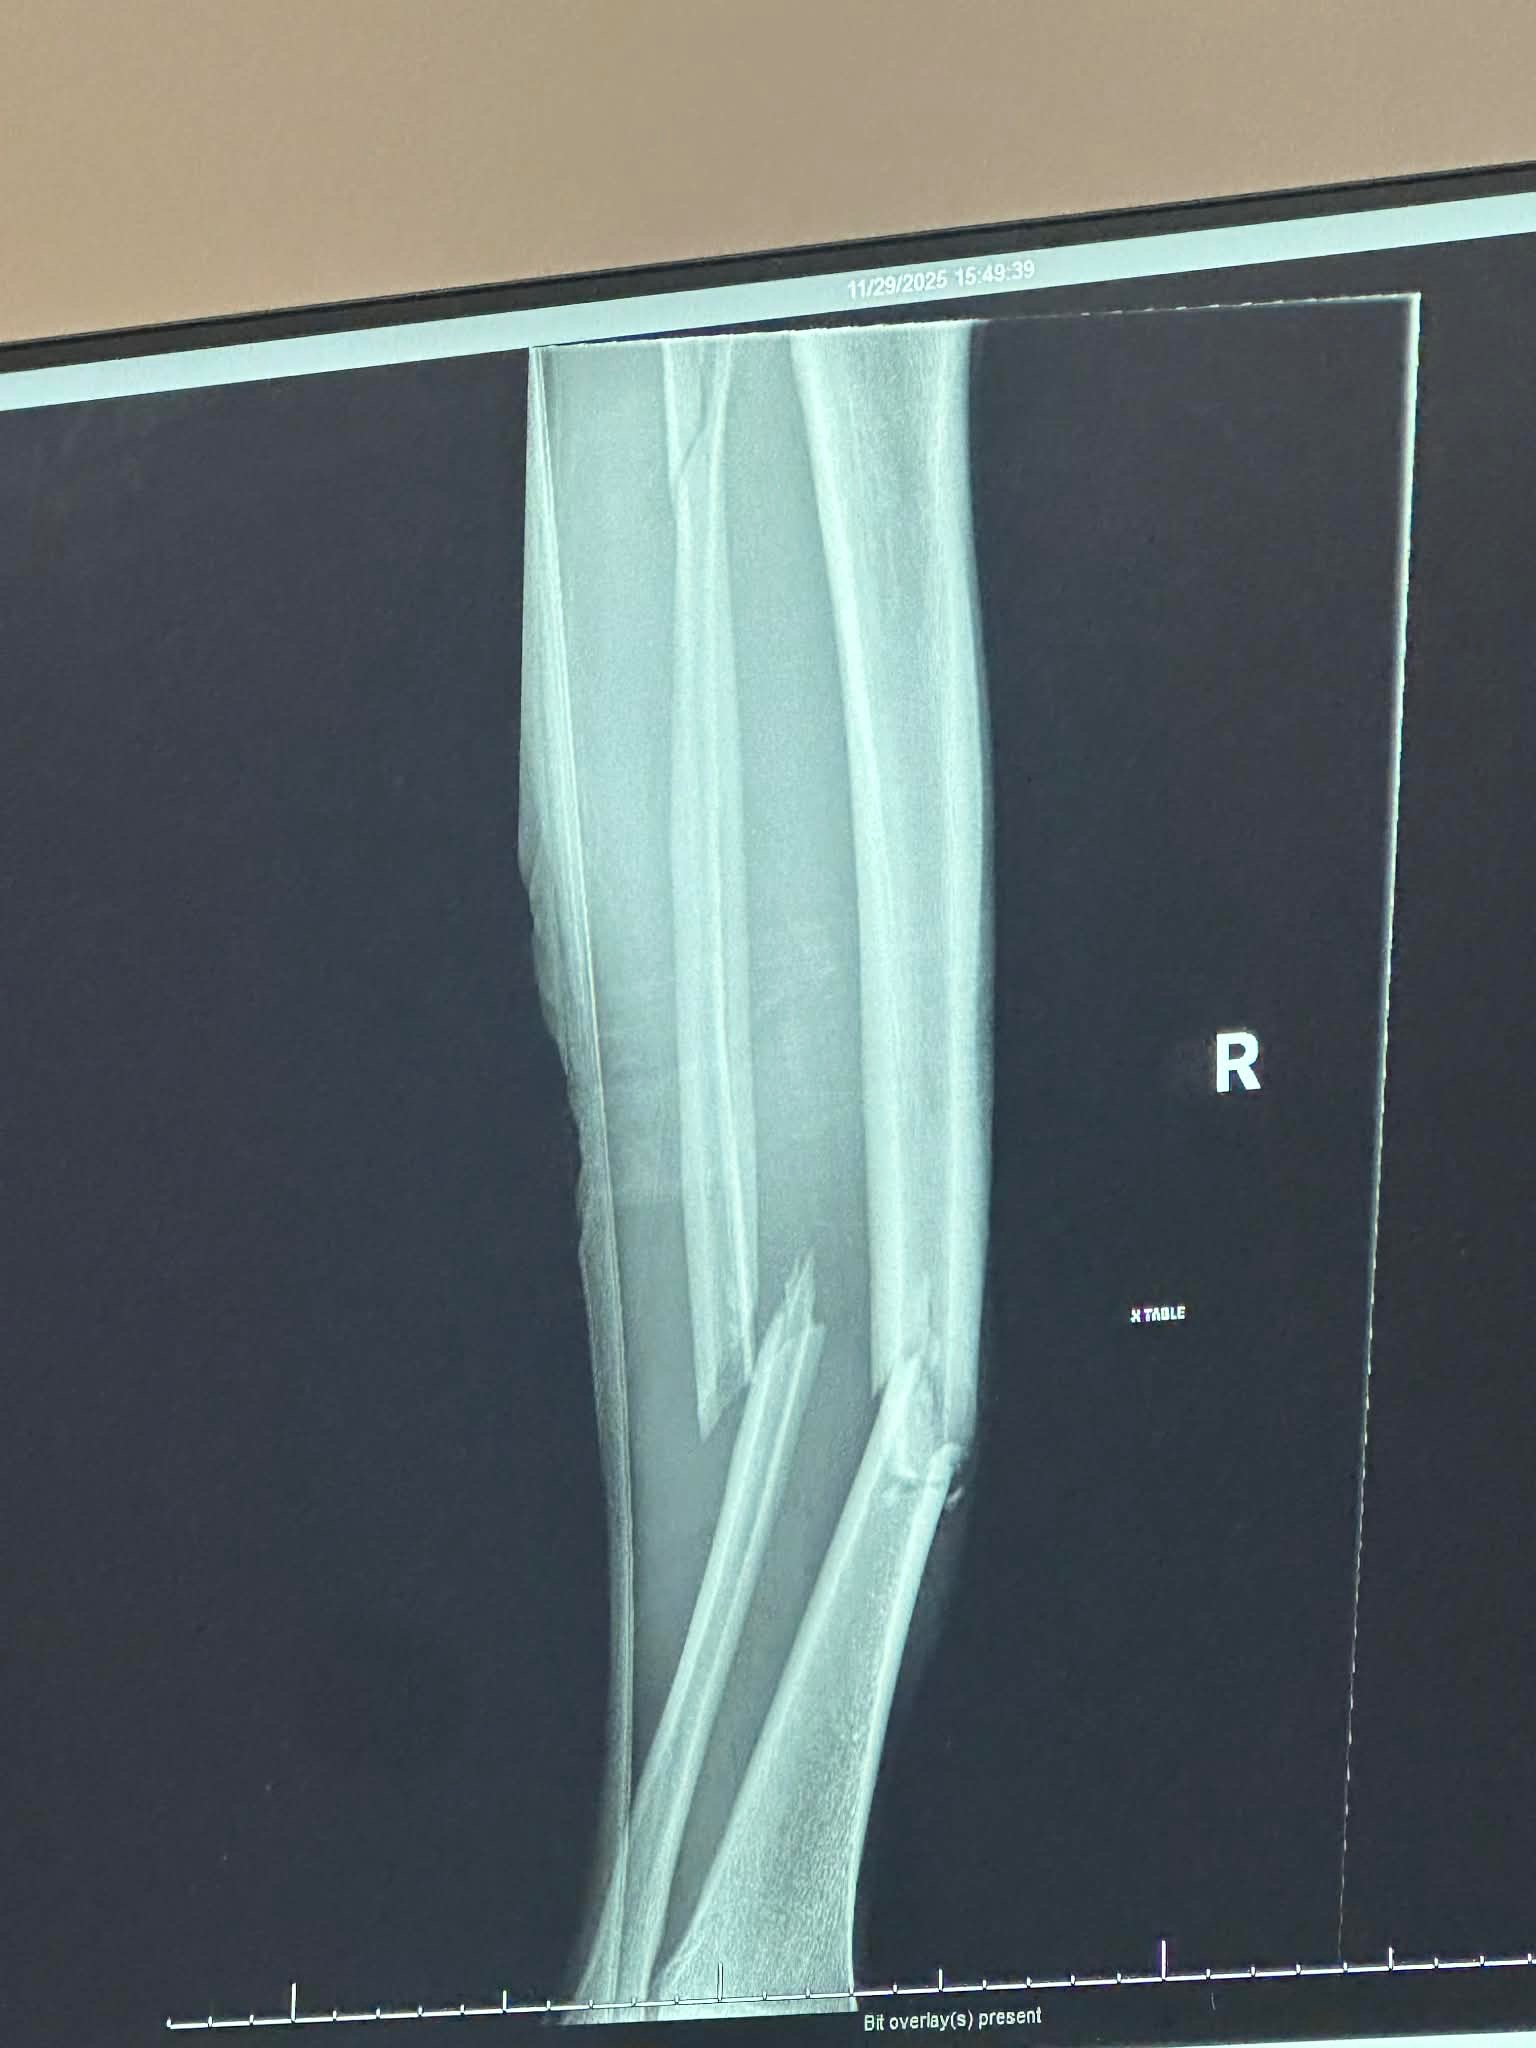

On November 29th, my dear friend, Tyler Ward, was riding his bike to the firehouse he volunteers at to respond to a call. In his travels, he collided with a minivan, and his leg was pinned under the tire of the van. Tyler was transported to Lehigh Valley Hazleton and then transferred to Geisinger Wyoming Valley, where he had to get surgery. He has multiple broken bones and also had to get a rod inserted into his leg.